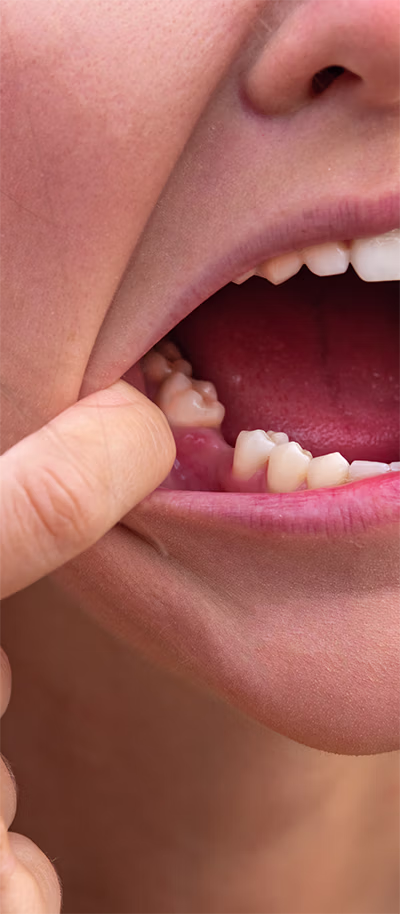

Impacted teeth occur when a tooth fails to fully emerge through the gums. This is common with wisdom teeth, some permanent teeth, and stubborn baby teeth. Causes can include overcrowding, abnormal growth patterns, or excess teeth in the jaw. Impacted teeth may lead to pain, difficulty chewing, or misalignment. In some cases, symptoms are not visible until detected on an X-ray. At our Leander office, we provide customized solutions for impacted teeth, including orthodontic guidance to help teeth erupt correctly. For problematic wisdom teeth, expert extraction is often the recommended solution.

Third molars, or wisdom teeth, typically appear in late adolescence or early adulthood. They often cause complications due to insufficient space for proper eruption, leading to:

- Pain and swelling

- Decay and gum infection

- Misalignment of surrounding teeth

- Cysts or tissue damage

Almost 90% of adults experience at least one impacted wisdom tooth. Our Leander dentists are trained to remove wisdom teeth safely and comfortably, protecting surrounding teeth, nerves, and tissues.